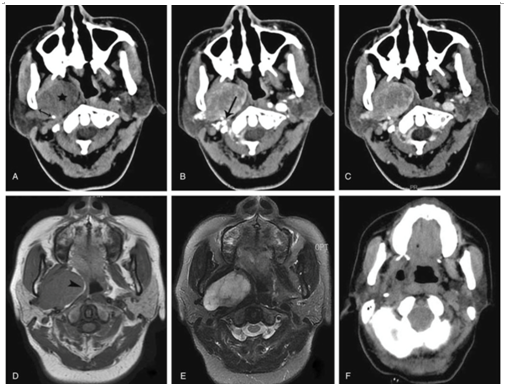

一位48岁的中国女性于2016年4月来到耳鼻喉科门诊,她有间歇性右口咽部反复绞痛3个月的病史。体格检查显示右侧口咽侧壁隆起,无异常分泌物或溃疡。口外检查肿胀、压痛或淋巴结肿大隐性。随后的CT和MRI显示在右PPS中有椭圆形60×40毫米的肿块(图4)。

图4

在完全切除和止血后,使用内窥镜进一步评估残余腔(图6)。术中出血量为200mL,肿瘤较大,大小为60×40×30 mm,紧贴颈内动脉和颈静脉。被覆完整包膜,血管丰富,在手术过程中容易出血。

图6

术中冰冻切片显示肿瘤来源于涎腺。常规组织病理学检查显示包膜实性肿块,颜色为白灰色,由两层排列成筛状或管状的肿瘤细胞组成。免疫组化结果显示,CK(PAN)、p63阳性,SMA、CD43、GFAP阴性。S-100阳性肿瘤细胞阳性。某些肿瘤细胞对CP、CD117和CK18呈阳性反应。Ki-67弱染色,MIB-1指数低于10%。最终诊断为BCA,术后病程平稳,术后5天出院,无并发症。CT扫描在术后2周显示模糊的右PPS,没有残留病灶的迹象(图7),随访到2017年12月。